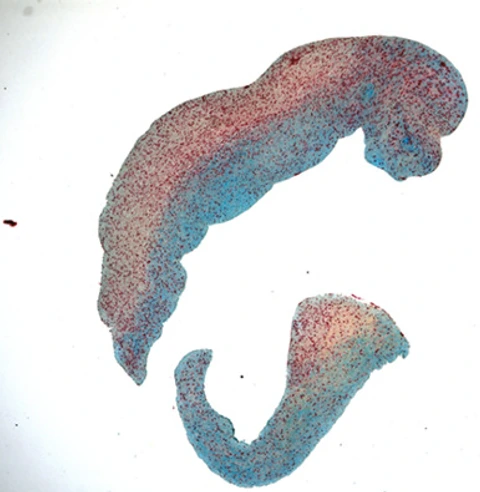

Querschnitt Posterior Tibial Arterie

The Applied Vascular Research Group aims to truly explore mechanisms of arterial and venous vascular disease by integrating molecular research, large animal models, first-in-man studies and multicenter clinical trials. One core research focus is to tackle restenosis, the Achilles heel of peripheral vascular interventions, by identifying patients at risk and developing improved treatment options. As peripheral arterial disease contributes to significant morbidity and mortality and is still severely understudied, there is an urgent need to improve both routine patient care as well as our knowledge on the mechanisms and outcomes of the disease.